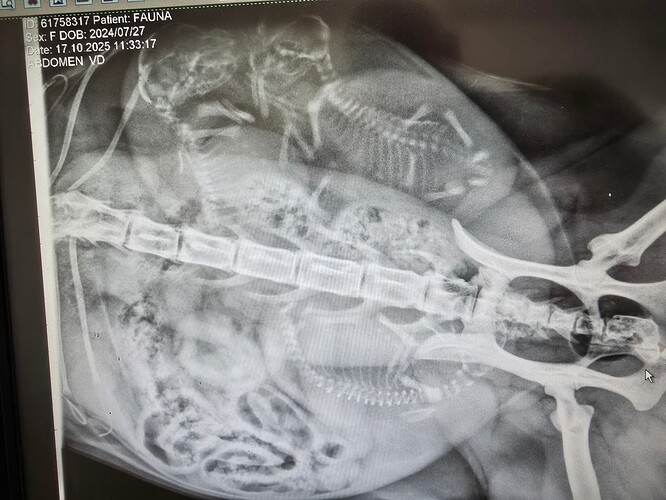

Så har vi været en tur forbi dyrlægen og fået taget røngten.

Hvor mange kan i tælle ??

Spurgte om de var korthåret eller langhåret :flojte: men det kunne hun ikke svare på :never: efterfulgt af et rapt svar: der er to drenge og en pige :tonguenanananana:

Jeps der er 3 styk og som _DK_Sugieh skriver, så kigger man efter rygsøjler og ser om der er samme antal hoveder, så er man sikker på at have talt rigtig.

Jeg tror det er et fint antal til hende, hun er trods alt kun 1 år og 3 måneder, så er forholds vis ung mor

Syntes jeg kan se 2 hoveder og 1 “ekstra” rygrad, så gætter på 3 (hele) killinger :smiley: